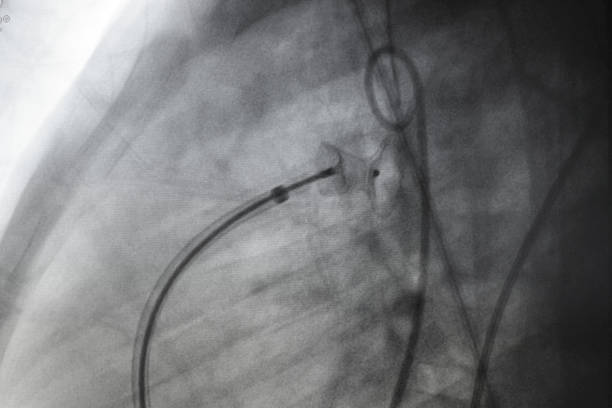

カテーテル先端にPt(プラチナ)コイルやチューブを装着し、マーカーとして使用するのが一般的ですが、Pt(プラチナ)は価格が非常に高く、極小のチューブやコイルでも部品単価として高額です。

Paliney-Invivoは白金と同系列のPd(パラジウム)を主元素とする合金で、不透過性、機械特性も既存のPt-IrやPt-Niと比較しても、同等の性能を有しており、Ptに比べ価格が安価で安定しているPdを主元素としており、既存の貴金属部材に比較し大幅なコスト低減が可能な新材料です。

Pdは生体適合性のある合金として実績があり、その市場価格もPtに比較すると大分安価です。高いX線不透過性を必要とする、各種の医療用途(血管治療用ガイドワイヤーやステント等)への応用が期待できる、新材料です。